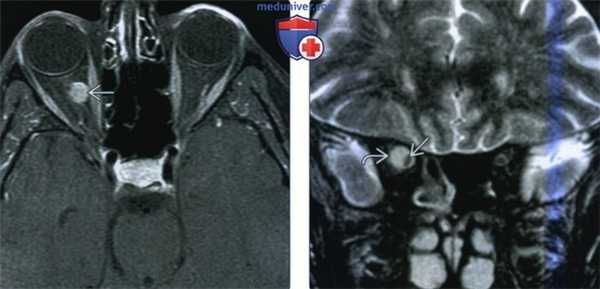

(Слева) На рисунке аксиального среза глазницы показана веретеновидная менингиома, развившаяся из влагалища зрительного нерва. Характерная «периневральная киста» позади глазного яблока представляет собой замкнутое между оболочками зрительного нерва скопление спинномозговой жидкости.

(Справа) При КТ с КУ в аксиальной проекции определяется контрастируемая менингиома влагалища зрительного нерва с точечными и линейными кальцинатами, окружающая комплекс левого зрительного нерва и прорастающая через верхушку глазницы. Обратите внимание на прилегающий гиперостоз. (Слева) При МРТ Т2ВИ FS в аксиальной проекции определяется глобулярная менингиома, поражающая внутриглазничный сегмент правого зрительного нерва. Т2-сигнал аналогичен сигналу паренхимы головного мозга. Менингиомы влагалища зрительного нерва, как и внутричерепные новообразования, на Т2ВИ иногда относительно гипоинтенсивны.

(Справа) При МРТ Т1 ВИ FS в аксиальной проекции определяется глобулярная конфигурация интенсивно контрастируемой менингиомы влагалища зрительного нерва, эксцентрично окружающей глазничный сегмент правого зрительного нерва. Характерно, что опухоль не распространяется на сегмент зрительного нерва непосредственно позади глазного яблока.